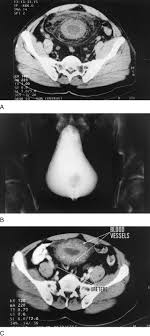

Ppt Pelvic Ct Scan Powerpoint Presentation Free Download Id 1882461

Pelvic Lipomatosis Associated With Proliferative Cystitis Occurring In Two Brothers Urology